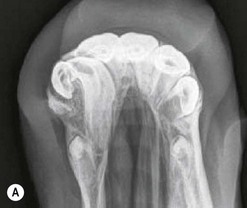

image image image

Fig. 13.36 Polydontia. Supernumerary maxillary cheek teeth (Triadan12s) are the most common supernumerary cheek teeth in horses. The 12 is usually markedly overgrown as in (A) but may be unerupted as in (B) if there is inadequate space (overcrowding). Note the abnormal shape of the apical area of the 112. (C) An example of overgrown bilateral supernumerary mandibular 12s.